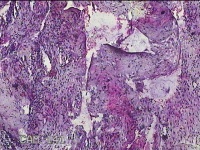

右卵巢囊肿壁

性别

女

年龄

36岁

临床诊断

右卵巢子宫内膜异位囊肿 盆腔炎性疾病后遗症

一般病史

痛经5年,加重3月。

标本名称

大体所见

灰白暗红色囊壁样组织4.5x3.3x0.8cm一堆,表面光滑,因已切开,囊内容物已流失,囊壁厚0.1cm。

图1